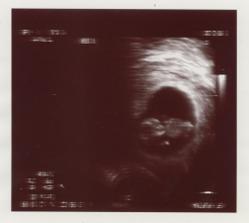

Výsledok nášho snaženia